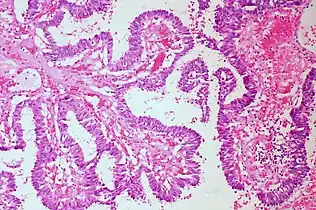

Interpretation

The histological slides are examined under a microscope by a pathologist, a medically qualified specialist who has completed a recognised training program. This medical diagnosis is formulated as a pathology report describing the histological findings and the opinion of the pathologist. In the case of cancer, this represents the tissue diagnosis required for most treatment protocols. In the removal of cancer, the pathologist will indicate whether the surgical margin is cleared, or is involved (residual cancer is left behind). This is done using either the bread loafing or CCPDMA method of processing. Microscopic visual artifacts can potentially cause misdiagnosis of samples.

Following are examples of general features of suspicious findings that can be appreciated from low to high magnification on histopathology:

Architectural patterns

Major histopathologic architectural patterns include:

Nuclear patterns

Major nuclear patterns include: